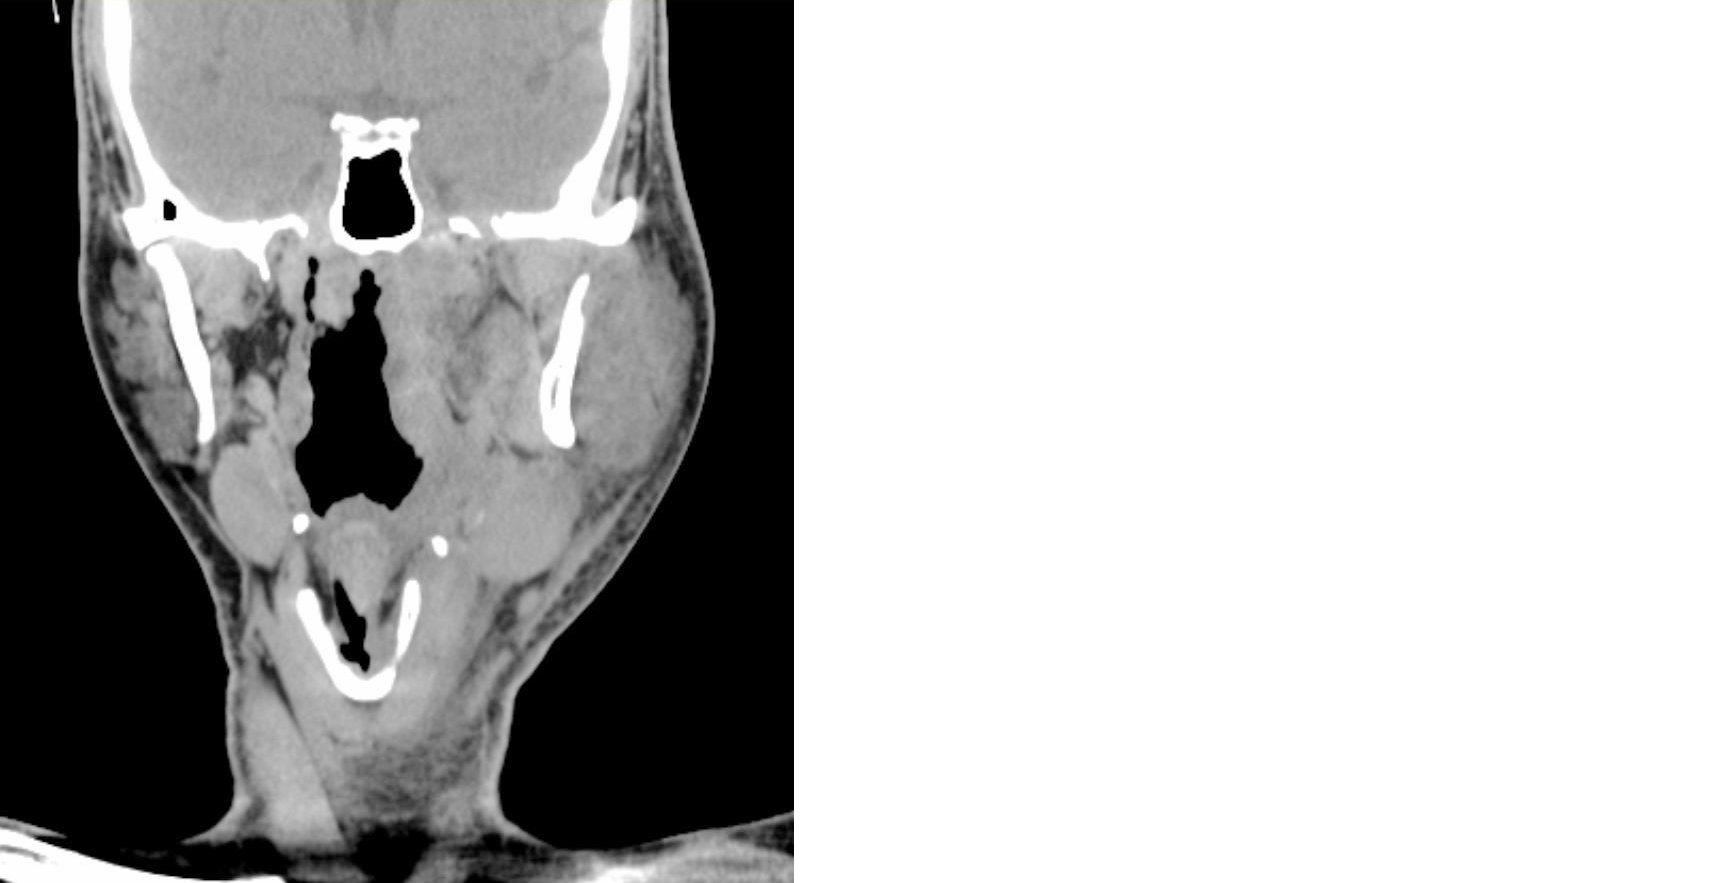

On clinical examination, there was a tender, diffuse swelling over the left submandibular and parapharyngeal regions, with markedly restricted mouth opening and palpable cervical lymphadenopathy on the left side. Oropharyngeal examination was limited due to trismus but revealed bulging of the left lateral pharyngeal wall. Ultrasonography demonstrated a collection within the left masseter space extending into the masticator space, suggestive of abscess formation. Contrast-enhanced CT of the neck revealed an ill-defined collection with peripheral enhancement extending from the submandibular to the parapharyngeal and retropharyngeal spaces, consistent with a deep neck space abscess (Figure 1). Associated left cervical lymphadenopathy was also noted.

Figure 1: CT neck plain (Coronal view) showing Ill-defined collection extending from submandibular to parapharyngeal spaces.